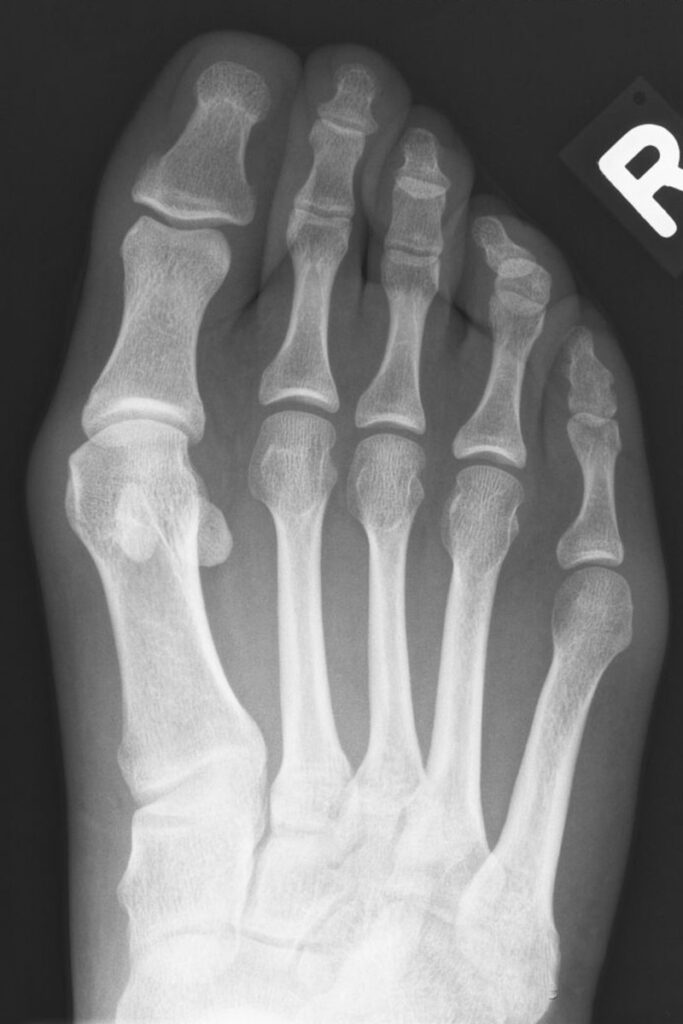

Fußchirurgie Röntgen nach Scarf

nach Operation (Scarf-Osteotomie)